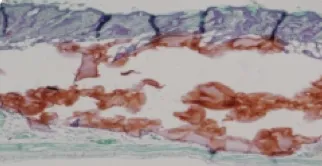

優越的組織相容度

良好的組織相容度,是注射後呈現然效果的關鍵!

在病理切片下,仙女玻尿酸顯出良好的膚相容性與耐受度,注射後與膚周圍的組織很好地融合,呈現然外觀。

注射前組織

仙女玻尿酸

他牌雙向玻尿酸